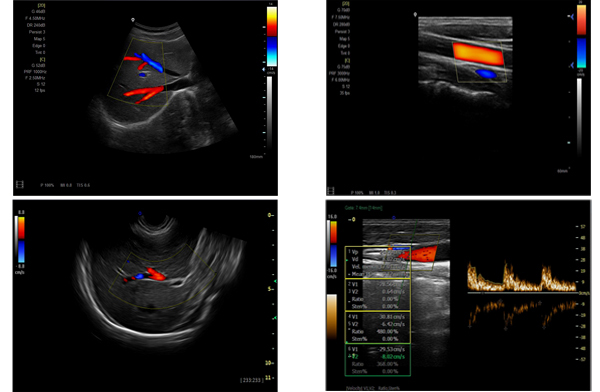

為高集成數字式彩色多普勒系列產品之一,廣泛實施于腹部,產科,婦科,血管,小器官,泌尿,新生兒和兒科等臨床,屬全身應用型彩色多普勒儀器。

●全身應用型包含2D/CFM/PDI/PW/ M等掃描模式;